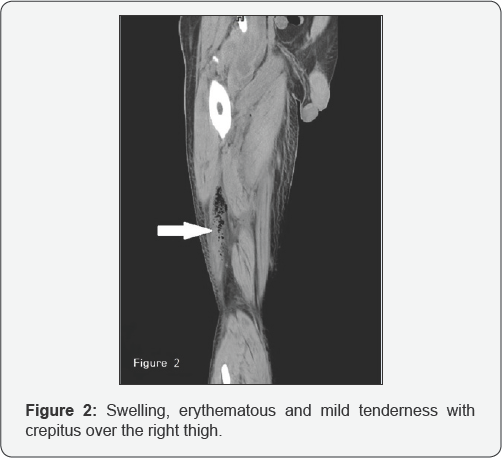

Fever with lethargy, even altered mental status is commonly seen in daily practice, especially in infected elderly. Recently we saw a 63 years old man who complaints of right thigh redness and tenderness for two days. But the etiology behind the scenes is perforated cecal tumor. Prudent workup of infectious source is mandatory to prevent from misdiagnosis. We also briefly review the literatures of necrotizing fasciitis of thigh secondary to perforated colon cancer. This old man went to our emergency department (ED) and said he also felt right back pain and difficulty in standing for one week. There was no symptom of fever, abdominal pain, nausea and vomiting, recent weight neither loss nor bowel habit change. His vital signs showed body temperature of 36°C, respiratory rate of 20 breaths per minute, pulse rate of 93 beats per minute and blood pressure of 92/54 mm Hg. Physical examination revealed swelling, erythematous and mild tenderness with crepitus over the right thigh (Figure 1).

Abdomen was palpated soft with tenderness over the right lower quadrant of abdomen. Laboratory data revealed white blood cell (WBC) count of 8,400/μL, band of 8%, neutrophil of 82%, hemoglobin of 12.4g/dL, platelet count of 36,000/μL, aspartate aminotransferase (AST) of 79 U/L and C-reactive protein (CRP) of 32.25mg/dL. Computed tomography (CT) of right thigh showed scattered, abnormal air accumulation in the subcutaneous layer and muscle layer of right thigh (Figure 2). Further, abdominal contrast-enhanced CT scan showed right colon tumor with abscess formation involving right retro peritoneum and psoas muscle (Figure 3). We applied empiric antibiotic therapy with teicoplanin 200mg and meropenem 500 mg intravenously every 12 hours and fluid resuscitation. Patient received emergent laparotomy and debridement. A 5 cm x 4 cm ulcerative tumor found at cecum and perforated to retroperitoneal space.